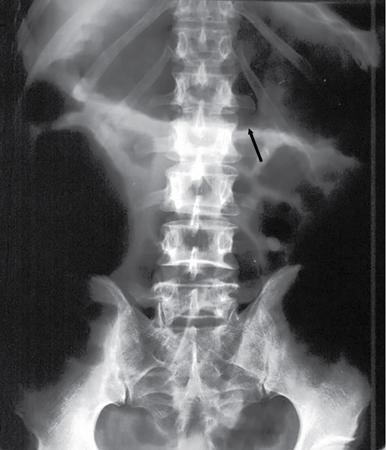

UNDERSTANDING THE ADULT ABDOMINAL RADIOGRAPH: TECHNIQUES AND INTERPRETATION Tanvi Modi Radiography of the abdomen is a common practice for the evaluation of abdominal organs. The anatomy and pathology of digestive, hepatobiliary and genitourinary systems can be assessed using radiographs, either as a stand-alone practice or as a primary imaging modality followed by contrast studies, ultrasound or cross-sectional imaging. In addition, abnormalities of the musculoskeletal or integumentary system can also be deduced on the basis of abdominal radiographs. This chapter intends to give an overview on the techniques and positioning in abdominal radiography as well as interpretation of normal and abnormal features. While superior imaging modalities such as ultrasound, computed tomography (CT), magnetic resonance imaging, capsule endoscopy and the likes have taken over abdominal imaging by and large, radiography still holds a pivotal role in certain situations and conditions, such as: The standard abdominal radiograph is taken in supine position and anteroposterior projection. This is also popularly known as the KUB (kidneys-ureters-bladder) radiograph. Previously, supine as well as erect radiographs were performed in all patients; however, this is not commonly done due to high-radiation dose. For all indications of abdominal radiography, including acute abdomen, supine radiographs are sufficient in terms of radiographic diagnosis, with the exception of perforation for which an erect chest or lateral decubitus radiograph can be performed if there is clinical suspicion. Patient should lie supine on the imaging table with median sagittal plane at right angles to the table and coincident with the midline of the table (Fig. 7.1.1.1). The body is divided into equal right and left halves by the median sagittal which passes through the sagittal suture of the skull. Pelvis should be adjusted so that the anterior superior iliac spines are equidistant from the table top. Gonadal shields, in the case of male patients, should be placed with the upper edge of the shield at the level of pubic symphysis. Although rarely used for female patients, these should be positioned between the anterior superior iliac spines and the pubic symphysis. The centre point of the image receptor should be approximately located at a point 1 cm below the line joining the iliac crests. The X-ray beam should be in a vertical direction, perpendicular to the table top and image receptor at the centre point. Collimation should be such that the soft tissue and subcutaneous region along lateral aspects of the abdominal cavity should be covered within the image. Also, the superior extent involving diaphragm and inferior extent involving the inferior pubic rami is important to look for any lower chest pathologies or any inguinal hernia. 35 × 43 cm (14 × 17 inches) in portrait orientation. On an average, abdominal radiograph exposes a patient to a dose of approximately 1.5 mSv, which is equivalent to 75 chest radiographs or 1/6th dose of a standard CT of the abdomen. The entrance skin dose is approximated to be 4 mGy. At such an effective dose, the additional lifetime risk of fatal cancer is 1 in 30,000. The exposure time is kept short. Patient is asked to exhale completely and hold their breath, with exposure taken at this point of full expiration to ensure imaging of abdominal organs in their natural positions. Modifications of this technique can be made depending on patient habitus and clinical condition. Kilovoltage peak (kVp) should be set to allow adequate visualization of abdominal soft tissue structures as well as semiopaque renal and biliary calculi. Average kVp is set at 70–85 kV. 102 cm (40 inches) Grids are commonly used to reduce scatter radiation. Placement of side marker on the image receptor at the time of radiographic exposure is essential. Bowel pattern depiction should be such that there is minimal lack of sharpness. Standard guidelines for abdominal radiography dictate that the radiograph should extend from the diaphragm up to the level of inferior pubic rami and must include the lateral abdominal wall musculature. The abdomen is divided into four quadrants on the basis of two perpendicular lines (Fig. 7.1.1.7). The vertical line passes through the mid sagittal plane and crosses the umbilicus and symphysis pubis. The horizontal line is a transverse line across the umbilicus at 90 degrees to the vertical line and is situated at the level of L4–L5 intervertebral disc. The quadrants are as follows: Another division system is dividing the abdominopelvic cavity into nine regions using two vertical and two horizontal planes (Fig. 7.1.1.8). The vertical planes, also known as the right and left lateral planes, are parallel to the midsagittal plane between midline and anterosuperior iliac spines on either side. Of the two horizontal planes, the upper transpyloric plane is at the level of lower border of L1 and the lower transtubercular plane is at the level of L5. The nine regions are: On a standard radiograph, the exposure should be such that the stomach, bowel loops, outlines of liver, spleen, kidneys, psoas muscles should be well identified. Also, lumbar transverse processes should be seen. Arch of the pubic symphysis should be visible to evaluate bladder region. A well-centred film without rotation will demonstrate bilaterally symmetrical lower ribs, iliac wings, ischial spines and obturator foramina. Different structures seen on an abdominal radiograph can be classified into five basic densities: Identification of different structures depends on the relative degree of contrast between their densities. The demarcation is clearer in chest and is diminished in abdomen due to relative similar soft tissue density of various structures. On a normal radiograph, relatively large amounts of gas in stomach and colon with minimal small bowel gas can be seen. Further, colonic gas can vary from negligible to extensive, mimicking obstruction pattern; however, usually the gas is enough to delineate colonic haustral pattern. Faecal matter gives a mottled appearance to colonic gas. Short-air fluid levels on an erect radiograph may be seen even in normal cases. The normal appearance of small bowel loops on an abdominal radiograph follows the rule of threes: Stomach is seen in the left upper quadrant and is visualized when distended with air. It is commonly seen extending from T11 to L2 level. Common feature identifying the stomach is the fundal gas which is usually seen as an air fluid level within the gastric lumen. Small bowel loops are distributed to the centre of the abdominal cavity and large bowel loops are peripheral. Duodenum is predominantly situated in right upper quadrant. It extends to left upper quadrant in the region of duodenojejunal flexure. Jejunum occupies the left upper and lower quadrants and is easily identified due to the presence of thick, numerous, closely spaced valvulae conniventes (Fig. 7.1.1.9A). The ileum occupies both lower quadrants and extends into right upper quadrant. Ileum has few and less prominent valvulae as compared to jejunum (Fig. 7.1.1.9B). Ascending and descending colon are retroperitoneal and have relatively fixed positions along lateral aspect of the abdominal cavity on either side. Transverse and sigmoid colon, on the other hand, may have a variable position due to their mobility along mesocolon and redundant pattern. These can be identified with confidence on account of haustrations and faecal matter (Fig. 7.1.1.10). Haustrations are usually well seen in ascending and transverse colon and poorly delineated beyond splenic flexure. Caecum is in the right lower quadrant, though it may be mobile or pulled up. Rectal gas is usually seen in the midline at the level of pelvis and its presence rules out large bowel obstruction. All these positions may vary due to anatomical conditions such as malrotation or pathological conditions, for example volvulus. Liver, spleen and renal outlines cannot be completely traced with precision due to the overlap by bowel loops. On a frontal projection, the liver appears as a triangular structure occupying right and left hypochondrium and epigastric region. Occasionally, the right lobe may be seen extending lower than the right renal shadow. This is a normal variant known as Reidel’s lobe. Gall bladder is situated in the posterior and inferior region of the liver and any pathology of the gall bladder should be looked for in this region. On a lateral radiograph, the gall bladder is anterior to the midcoronal plane. This helps in distinguishing gall bladder calculi from renal calculi, which will be more posteriorly situated. Spleen is seen in left upper quadrant/left hypochondrium, flushed to left lower ribs and left hemidiaphragm. Pancreas is present in the epigastric region (right and left upper quadrants) and is usually not identified in the absence of a pathology. The kidneys are bean-shaped retroperitoneal organs which are seen on either side of the vertebral column and lateral to psoas muscles. Due to the presence of liver on the right side, this kidney is slightly lower in position as compared to its contralateral counterpart. The visualization of kidneys on radiographs is facilitated by the surrounding fatty capsule. Kidneys lie between T11–12 and L2 level, with left kidney 1 cm higher than the right. Psoas muscle shadow can be normally seen along lateral aspect of lumbar spine bilaterally and is mildly concave (Fig. 7.1.1.11). Abdominal wall muscles are not routinely assessed on radiography; however, inclusion of lateral abdominal wall (muscles as well as subcutaneous plane) is a must while performing radiography. The flank stripe or the properitoneal fat stripe is a fat density linear concavity seen along lateral abdominal wall (Fig. 7.1.1.11). It is bound by the paracolic gutters and air-filled ascending and descending colon. All the solid organs in the abdomen are identified due to the fat density outlining them. Distortion of these fat lines helps in identifying organomegaly or focal mass lesions. The dome of urinary bladder is outlined by fat, which aids in differentiating its density from other soft tissue structures of the pelvis. Not all calcifications seen on abdominal radiograph are abnormal. Some may depict age-related changes such as vascular calcifications involving abdominal aorta, pelvic vessels, splenic artery in the region of left upper quadrant. Within the pelvis, phleboliths may be seen and mistaken for urinary calculi. Assessment of lumbosacral spine, iliac bones and femoral heads can be made on the basis of plain radiography. Degenerative changes may be commonly seen. Lower ribs can also be evaluated for pathologies. Dilated small bowel loops with rounded soft tissue density in midline over umbilical region suggests obstruction secondary to umbilical hernia. Pneumoperitoneum must be looked for in all cases of acute abdomen. While erect chest and left lateral decubitus radiographs can detect even 1 mL of free air, there are multiple signs on supine radiograph to suggest this diagnosis, for example Rigler’s sign, falciform ligament sign, football sign (Figs. 7.1.1.24 and 7.1.1.25). Retroperitoneal perforation may demonstrate air outlining psoas muscles and retroperitoneal organs. Small amount of free air may persist in the abdominal cavity up to 3 weeks after surgery, although it usually resolves within a week. Clinical history is important in such cases. Air foci within the bowel wall may represent bowel ischaemia/strangulation. Linear gas patterns in right hypochondrium may be due to two causes, that is pneumobilia and pneumoporta. The former can be seen normally postbiliary surgery, sphincterotomy, ERCP or in the case of abnormal fistulous communication between bowel and biliary tree (Fig. 7.1.1.26A). Pneumoporta (Fig. 7.1.1.26B) is a red flag and warrants further investigation to look for conditions such as mesenteric ischaemia and toxic megacolon. Pneumobilia is more centrally located whereas air shadows in pneumoporta are seen reaching up to periphery of liver. Air foci over renal shadows (Fig. 7.1.1.27), gall bladder or pancreas, in the absence of recent procedural history, suggest fulminant infection and mandate urgent intervention. Central midline calcific foci between T9 and T12 vertebrae can be attributed to calcific pancreatitis (Fig. 7.1.1.28). In the left upper quadrant, areas of calcification seen involving a shrunken spleen may be seen in autosplenectomy. In right upper quadrant, calcified gall stones may be seen. These tend to be small, multiple, uniformly circumscribed and ring-like in appearance with central translucency (Fig. 7.1.1.29A). Mercedes Benz sign, a triradiate pattern of gas lucency, is associated with gallstones. In contrast, renal calculi are more commonly solitary, irregular, of homogenous density, conform to renal calyceal or pelvic outline (Fig. 7.1.1.29B) and are sometimes of staghorn configuration. On lateral view, the gall stones are more anteriorly located as compared to renal calculi, which may be partly superimposed on lumbar vertebrae. Ureteric calculi tend to overlap bony structures such as lumbar transverse processes (Fig. 7.1.1.29B) or sacroiliac joints. Extensive or patchy, curvilinear calcification of gall bladder wall is known as porcelain gall bladder which is often associated with malignant transformation. Calcification involving adrenal glands may be secondary to infection or haematoma, or a congenital condition known as Wolman’s disease where there is bilateral involvement. Discontinuous discrete midline tram track calcification in the abdomen may indicate atherosclerotic changes in abdominal aorta and branch vessels. However, when the calcification is in a globular pattern and seen below the level of L2 vertebra, aortic aneurysm should be suspected (Fig. 7.1.1.30). Appendicoliths, though not commonly seen, may sometimes be detected in right iliac region. Pelvic calcifications: vesical calculi, distal ureteric or vesicoureteric junction calculi, calcified fibroids, ovarian dermoid with tooth-like calcifications (Fig. 7.1.1.31) may be the cause of abdominal pain and should be diligently looked for. Vesical calculi are usually more large and central in location whereas calcification due to fibroids may be more lateral. Schistosomiasis is another cause of bladder wall calcification, as is calcification of bladder tumours. Phleboliths tend to be bilaterally symmetrical, with a lucent centre unlike ureteric calculi. While it is believed that phleboliths are located below the level of ischial spines and ureteric calculi above, this is not always true and should be confirmed with CT. Fluid may collect adjacent to properitoneal fat line, forming a linear soft tissue density separating the fat line from the ascending or descending colon. Hellmer’s sign demonstrates medial displacement of lateral edge of liver (hepatic angle), due to fluid collection or ascites. Gross ascites may appear as generalized abdominal haziness or diffuse increased density of pelvis. Abscesses can involve any solid organ and in such cases may be difficult to demonstrate on plain radiography alone. Enlargement of organ or faint gas densities within can be suggestive of the same. In the case of peritoneal abscess, mottled density due to air, fluid and necrotic contents point towards this diagnosis, especially in right iliac fossa in association with appendicitis. Retroperitoneal abscess, similar to any retroperitoneal mass, may cause displacement of retroperitoneal structures (Fig. 7.1.1.32). Subdiaphragmatic abscesses may show concomitant ipsilateral pleural effusion (Fig. 7.1.1.33). These should be differentiated from Chilaiditi syndrome. Fluid and soft tissue lesions present with the same density on radiographs. While it is difficult to characterize the lesion and organ of origin, clues for the same can be provided by organomegaly (Fig. 7.1.1.34), distortion of fat surrounding solid organs, displacement of bowel loops or solid organs. For example, a retroperitoneal lesion may cause anterior or inferior displacement of kidney, a pelvic mass may cause upward displacement of small bowel loops. Different densities such as fat or calcification may help in identifying organ of origin (e.g. fat and tooth densities seen in ovarian dermoid). Convexity of margins of psoas muscle on an abdominal radiograph can be due to haematoma, abscess or intramuscular tumour. Radiographs are performed for the initial diagnosis of foreign body in the abdomen including type, number of foreign bodies, location, size and shape (Fig. 7.1.1.35). Radiolucent foreign bodies such as wood, plastic, chicken bones will not be easily identified on radiography. Low kVp (65–70 kVp) can increase contrast and help identify these objects. In addition to an abdominal radiograph, chest radiography is also performed to exclude aspiration or oesophageal location of foreign body. Ingested or introduced foreign bodies may cause complications such as obstruction, perforation, fistula formation and sepsis. Hence, once their presence is confirmed, follow up radiography must be performed until they are eliminated. One must look for fractures/dislocation injuries involving the vertebrae or pelvic bones, especially after history of trauma. Lucent expansile lesions or sclerotic bony deposits which represent neoplasms, absent pedicle sign in cases of metastasis, metabolic bony changes such as rugger jersey appearance, Paget’s disease, arthropathies such as ankylosing spondylitis with bamboo spine appearance and sacroiliitis (Fig. 7.1.1.36) are some of the conditions which may be diagnosed based on an abdominal radiograph. Overlap of bowel loops over iliac blades may lead to a misdiagnosis of lucent lesions and should be evaluated with caution. Basal pneumonia may be the cause of acute abdominal pain and should be looked for in abdominal radiography. Similarly, pleural effusion, pericardial effusion, calcified pleural plaques, achalasia, interstitial fibrosis are few other findings that can be seen in lower chest on an abdominal radiograph. Basilar atelectasis can give a deceptive appearance of pneumoperitoneum (Fig. 7.1.1.37). Surgical clips, commonly in right hypochondrium after cholecystectomy, drainage tubes, ventriculoperitoneal shunts, femoral line catheters, IVC filters, stents (vascular, renal, biliary) (Fig. 7.1.1.38), stoma bags, contraceptive devices are some structures that may be seen in an abdominal radiograph. Correct knowledge of patient history and normal locations of these structures prevents misdiagnosis. Certain artefacts may be projected upon the radiograph due to surface structures such as trouser buttons, body piercing, sequins over clothing and should not be considered as a pathology. Multiple skin surface nodules in cases of neurofibromatosis, soft tissue focal swellings, such as abscesses, lipomas, haematomas, desmoid tumours and malignant lesions may be incidentally seen on radiography. These can be further evaluated using ultrasound or CT. Subcutaneous emphysema is another finding that may be seen in lower abdominal wall secondary to retroperitoneal perforation or diffusely along abdominal wall in the case of bowel perforation (Fig. 7.1.1.39). Foreign bodies such as bullets and pins may be seen lodged in abdominal wall. A systematic approach to abdominal radiographs is important for accurate diagnosis as follows: Despite the development of newer techniques for imaging of the abdomen, plain radiography still holds an important place in the initial assessment of acute abdomen. Positive and negative findings on an abdominal radiograph can direct further investigation. Ideal positioning, recognition of normal appearances and keen scrutiny for pathologies is a sine qua non for radiologists reading a plain film of the abdomen. OESOPHAGOGRAM Padma V. Badhe, Vikram Reddy, Sultan Moinuddin Shaukatali, Zillani Alam, Ravi Varma, Abhishek Bairy, Dasari Ravikiran, Revati Tekwani, Soniya Patankar, Megha Nair, Gautham Shankar Oesophagogram is the process of obtaining radiological images and simultaneous motion recording to evaluate function and disorders of pharynx, oesophagus and proximal stomach. Oesophagogram is usually done primarily to evaluate dysphagia. Some of the common indications are oesophageal motility disorders, strictures, gastro-oesophageal reflux disease (GERD) and suspected masses. It can also be used to detect uncommon anomalies like vascular rings/slings and aberrant anatomy. It also helps to evaluate further in cases where there is inability to pass upper GI scope. Double-contrast oesophagogram is mainly indicated in early mucosal disease like erosion, polyp, infection and tumours. If a motility disorder is suspected, dynamic technique (e.g. videofluoroscopy) is used for dysphagia or aspirations in cases of stroke, neuromuscular disorders, post head and neck surgery or radiation. Barium oesophagogram is contraindicated in suspected cases of perforation and tracheoesophageal fistula, aspiration, rarely if there is hypersensitivity to barium suspensions. It is also contraindicated in suspected oesophageal perforation where a water-soluble contrast agent is more suitable. However, ionic water-soluble contrast agent is better avoided in cases of aspiration or fistula with airway. The contrast examination of the pharynx is dangerous in cases of acute epiglottitis and must be ruled out on plain radiograph. An 80% w/v barium suspension is used in full column views. However, 200%–250% w/v barium suspensions is usually required for mucosal relief films. The barium sulphate mixture is fed to the patient either by spoon, by glass, or through a drinking straw, depending on its consistency. In videofluoroscopy, the pharyngeal phase of swallowing is usually safer with barium pudding than with thick barium and safer with thick barium than with thin barium. However, if the major abnormality is poor pharyngeal contraction leading to stasis in the piriform sinus (and epiglottic tilt is normal), a thin liquid is safer. Epiglottic motility is better assessed with thin barium because thick barium often obscures the epiglottic tip. Fluoroscopic equipment capable of cine fluoroscopy and capability for rapid sequence spot images (high frame rate) is needed for this examination, Barium suspension, straw, glass, Lead apron and radiation protective equipment. The patients are instructed to fast after midnight before the day of the examination. The pharynx should be made as dry as possible during the examination as high-density barium adheres to dry pharyngeal mucosa. Activities like smoking, chewing gum and lozenges must be abstained before the procedure as they impair barium coating by increasing the salivary secretion. Regular oral medications must be taken with sips of water; however, insulin must be skipped on the morning of examination. The major principles of a good oesophagogram includes mucosal coating, distension and projection. A routine oesophagogram consists of screening of the oral, pharyngeal and oesophageal phases of swallowing, single and double-contrast examination of pharynx, single contrast, double-contrast and mucosal relief views of the oesophagus. In cases of dysphagia, the examination is tailored depending on whether the symptoms are either pharyngeal or oesophageal and initial fluoroscopic findings. If patients’ symptoms are suggestive of oral or pharyngeal disorder then pharynx is evaluated first. Similarly, if patient is suspected to have thoracic oesophageal disease then, double-contrast examination of the oesophagus is performed before the pharyngeal evaluation. During an oesophagogram the positioning of the patient varies according to the type of examination (Table 7.1.2.1).